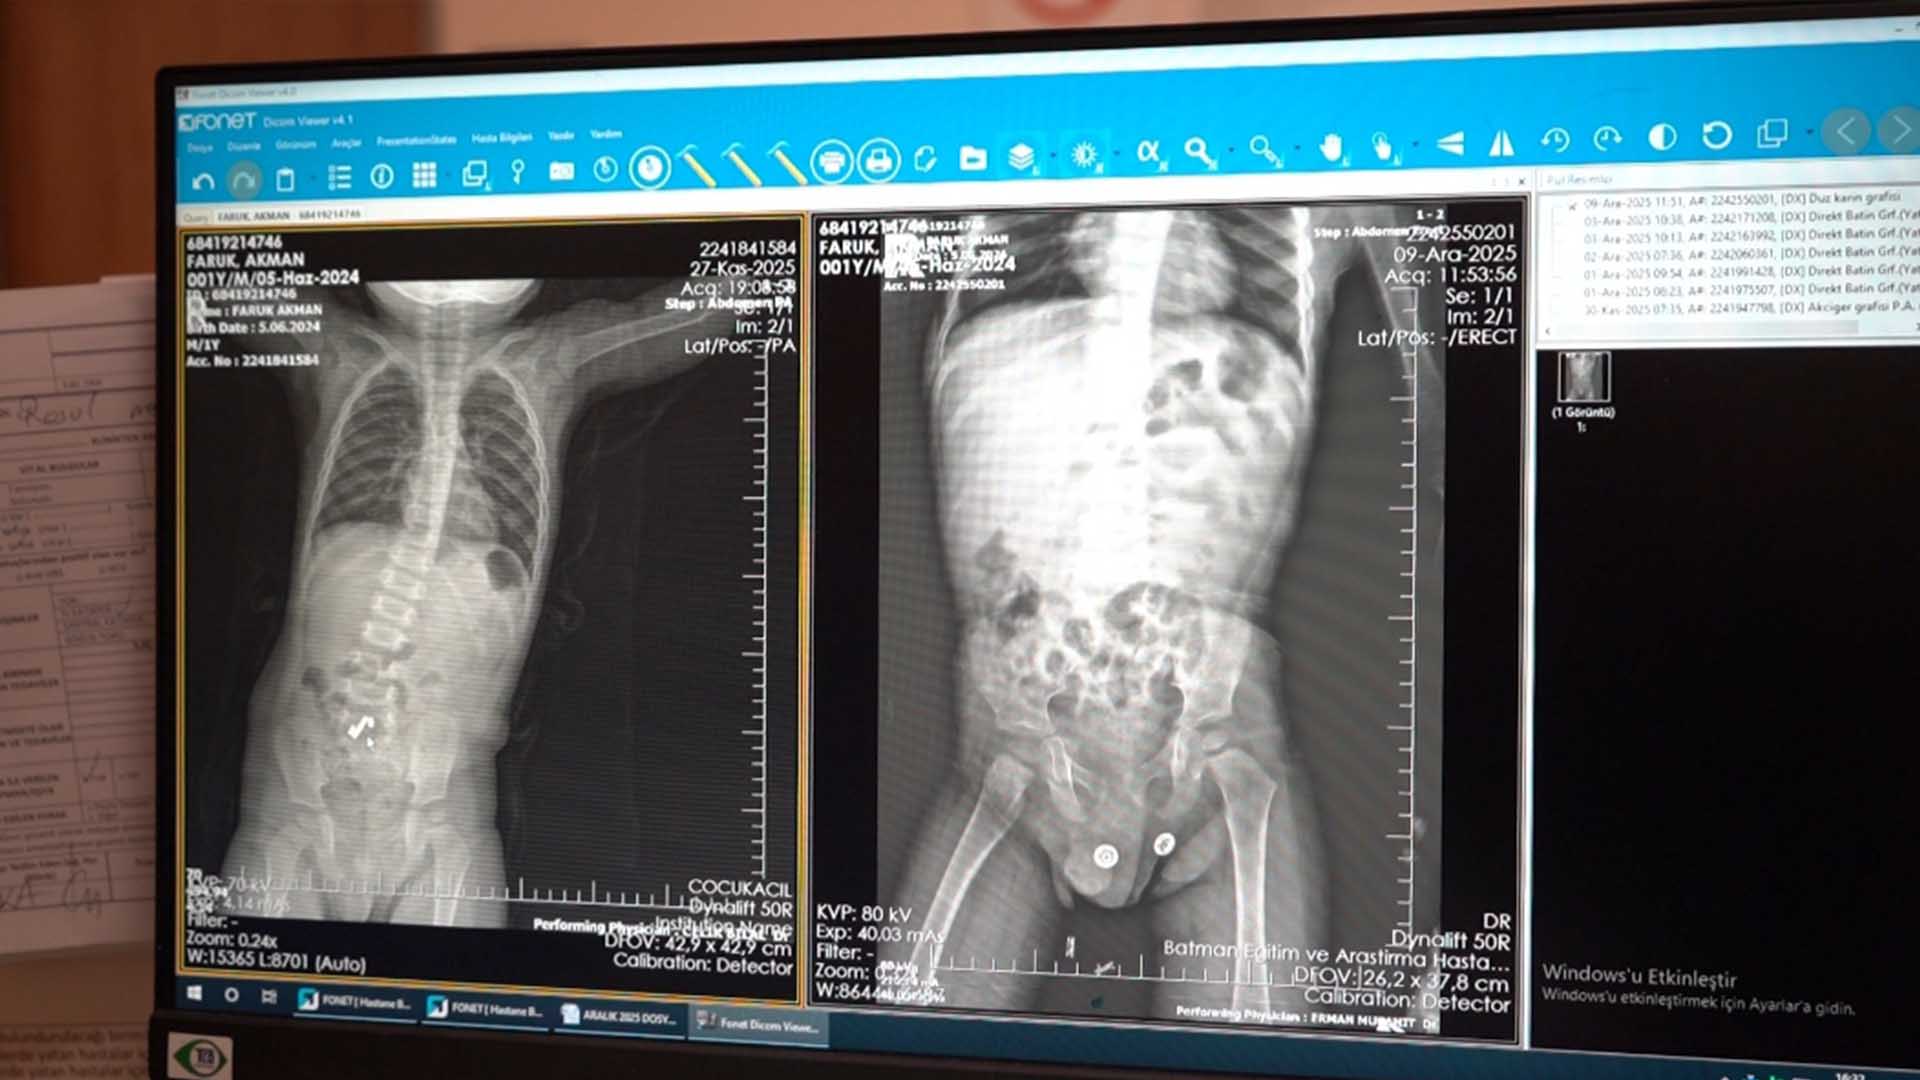

Batman’da mıknatıs yutan ve kusma, karın ağrısı şikayetiyle ailesi tarafından Batman Eğitim ve Araştırma Hastanesi Acil Servisi’ne getirilen Faruk Akman, ilk değerlendirme sonrası yakın takip amacıyla Çocuk Cerrahisi Kliniği’ne yatırıldı. Takipte mıknatısların sindirim sisteminde ilerlemediğinin görülmesi üzerine, çoklu mıknatısların bağırsak duvarlarına yapışarak delinmeye neden olabileceği belirtildi. Bunun üzerine tanısal laparoskopi kararı verildi. Operasyonda bağırsakların 3 farklı noktasında delinme tespit edildi. Çocuk Cerrahisi Uzmanı Op. Dr. Mücahit Erman ve ekibi tarafından yapılan laparoskopi destekli cerrahi müdahalede yaklaşık 5 santimetrelik hasarlı bağırsak bölümü, mıknatıslarla birlikte çıkarıldı. Operasyon sonrası genel durumu hızla düzelen Faruk Akman, beslenmesinde sorun görülmemesi üzerine taburcu edildi.

Op. Dr. Mücahit Erman ailelere uyarılarda bulunarak, “Hastamız karın ağrısı, kusma ve mıknatıs yutma şüphesiyle başvurmuştu. Acil serviste kendisini gördüğümüzde aileye detaylı bilgilendirme yaptık. Öncelikle takip amaçlı yatırdık. Takibinde mıknatısların batında bağırsaklar arasında ilerlemediğini gördük. Aynı bölgede kaldığı için aileye detaylı bilgi vererek, bunun bir cerrahi problem olabileceğini, mıknatısların bağırsakların duvarlarında bir erozyona neden olabileceğini düşündük. Bu nedenle operasyon kararı verdik. Hastaya operasyonumuzun kapalı yöntemle başlayacağını, bu tanısal işlemin gerekirse bir miktar küçük açık işlemle devam edeceğini söyledik. Aile sağ olsun, bize güvendi. Bu nedenle aileye de teşekkür ediyoruz. Ameliyatımızı başarıyla gerçekleştirdik. ERAS (ameliyat sonrası gelişmiş iyileşme) protokolleri gereği hastamızı ikinci günden itibaren beslemeye başladık. Takibinde beslenmeler ile ilgili herhangi bir problem olmayınca taburculuk kararı verdik. Genel durum iyi. Kozmetik açısından yarası gayet iyi. Çoklu mıknatıs yutmalarda özellikle birbirlerinin çekim gücüne bağlı olarak farklı zamanlarda alınan mıknatıslar, özellikle bağırsaklarda bu şekilde delinmelere neden olabiliyor. Bu nedenle ailelere dikkat etmelerini öneriyoruz” dedi.